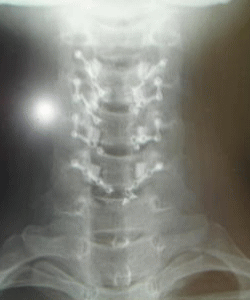

脊髄髄内腫瘍のCT画像(手術後)

撮影日:2010年1月15日

よく見ればチタンプレートが折れているのが分かります。

(左側の上から2番目)